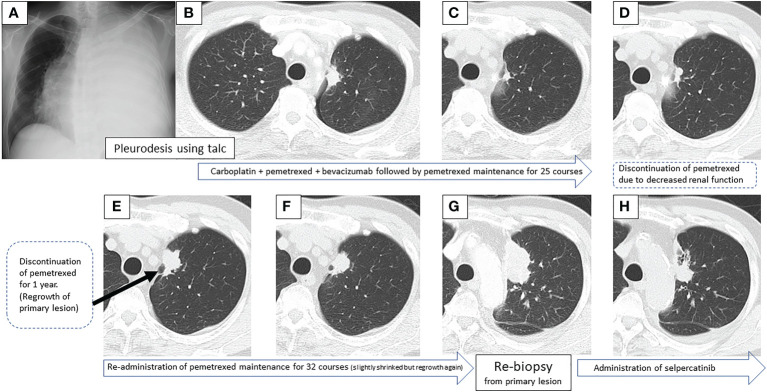

一名67岁的男性,从未吸烟,无显著病史,因为左侧大量胸腔积液(图1A)被转诊至佳学基因肿瘤基因检测病例交换医院。对左侧胸腔积液进行的细胞学评估显示V级腺癌,与细胞块病理评估一致。使用滑石粉进行胸膜固定后,肺部膨胀良好,左S1 + 2a处出现一颗25×17mm的结节,被认为是原发病灶(图1B)。临床上,他被诊断为腺癌T1cN3M1a,IVA期。初次基因突变筛查进行于七年前,使用其他机构的进行的EGFR突变和ALK免疫组化(IHC)测试结果均为阴性。

图1:在第一次就诊到开始进行第二次治疗期间,患者7年间原发病灶的顺序图像

一线治疗包括卡铂+培美曲塞+贝伐单抗,经过4个疗程后获得近乎完全缓解(CR),但鼻出血仍然持续,仅进行培美曲塞维持治疗。在维持治疗的25个疗程中实现了CR(图1C),但由于肾功能轻微恶化,治疗暂时中断。治疗结束后一年,CT显示原发病灶轻微进展(图1D),但复发速度较慢。确认CT复发一年后(图1E),重新开始培美曲塞单药治疗,原发病灶和淋巴结减小(图1F)。然而,在进行了32个维持治疗疗程后,出现了快速的全身进展。由于原发病灶再生(图1G)、对侧肺转移、多发性肝转移、右侧肾上腺转移和多发性脑转移(图2A、B),需要调整他的治疗方案。

通过支气管镜对原发病灶进行再活检,细胞学评估显示V级腺癌,组织学评估证实了这一结果。肿瘤精准用药850基因检测确认患者为RET融合基因阳性,随后于第二天给予240mg塞尔帕替尼。第13天的CT显示与基线影像相比(图1H),所有转移病灶,包括脑转移(图2C、D),均有良好的全身反应。由于2级肝酶升高,继续给予剂量减少的塞尔帕替尼(每天160mg)。使用高敏感度的下一代测序(NGS)面板系统:肺癌紧凑面板,并使用细胞学刷液进行RNA检测,证实了融合基因KIF5B外显子15;RET外显子12(K15RET12)。肿瘤精准药基因解码基因检测还能够从7年前的胸腔积液细胞块的福尔马林固定石蜡包埋(FFPE)标本中进一步确认RET(图3A、B),这些标本在恶性细胞的形态学上与再活检样本相似,具有大核仁(图3C、D)。从初始细胞块样本中收集到的RNA(1256ng)具有RNA整合数(RIN)值为4.8。单重PCR和NGS检测均检测到了K15RET12融合峰(图3)。